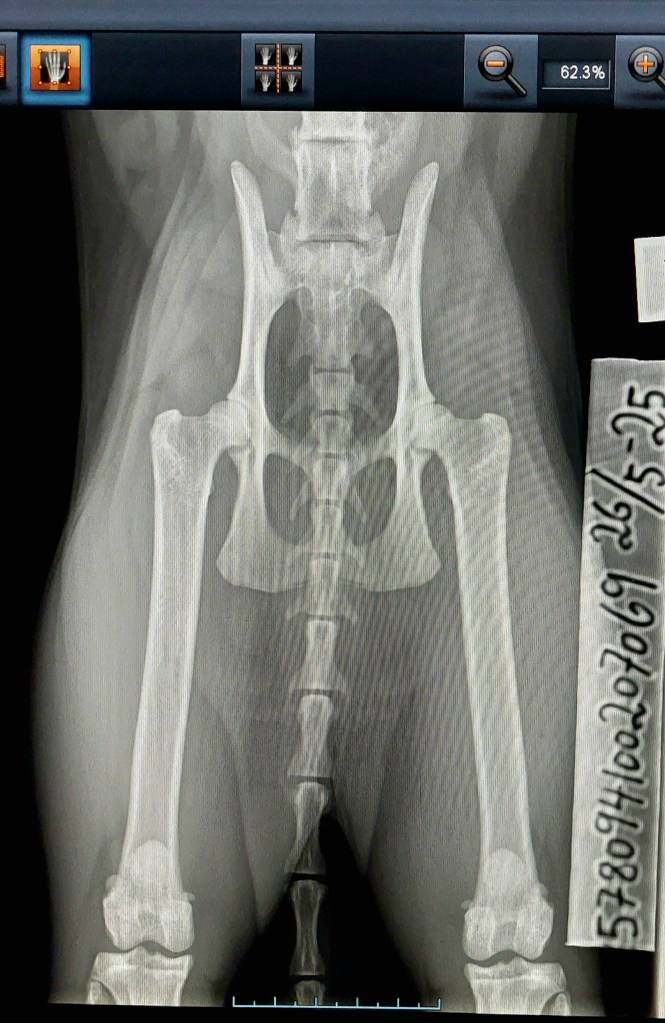

The time had come for my girl Zipporah, of the cattery’s third generation, to get her hips examined. The pictures have been submitted to OFA for evaluation. Now all there’s left to to is to wait, which is the absolute worst and nerv wrecking. I hope for the results to say dysplasia free or «good» by OFAs standard, but I’ll have to wait and see if that’s realistic or not.

Results will be posted below.

OFA has evaluated her hips to FAIR, which is free of dysplasia.